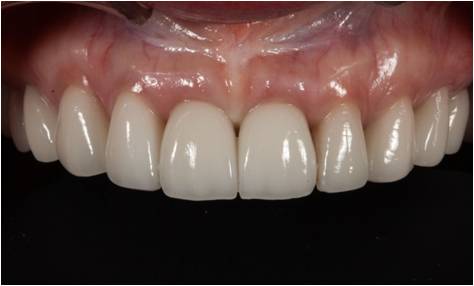

앞니에 결손이 있거나 치아를 뽑아낸 자리에 임플란트를 식립하여 자연치아의 기능을 회복시켜 주는 시술입니다.

앞니의 결손은 눈에 쉽게 잘 보이는 부분이라 환자의 미적인 결함이 두드러지게 되어 환자의 자신감을 크게 상실시키기 때문에

신속하면서도 심미적인 치료가 요구됩니다.

서울에스치과에서는 치아형태, 치아색조, 잇몸형태 3가지의 심미적인 조건을

만족할 수 있도록 임플란트 시술을 진행하여 만족도 높은 치료가 될 수 있도록 합니다.

앞니는 잇몸뼈가 얇아서 치아를 제거하고 나면 잇몸뼈가 빨리 줄어들기 때문에

시기를 놓쳐 얇은 잇몸 뼈에 임플란트를 심고 나면 환자 본래 치아와 어울리지 않는 상황이 올 수 있습니다.

따라서 앞니가 소실되어 임플란트 치료를 해야 하는 경우에는 최대한 빠르게 정밀 진단과 치료를 진행하시는 것이 중요합니다.